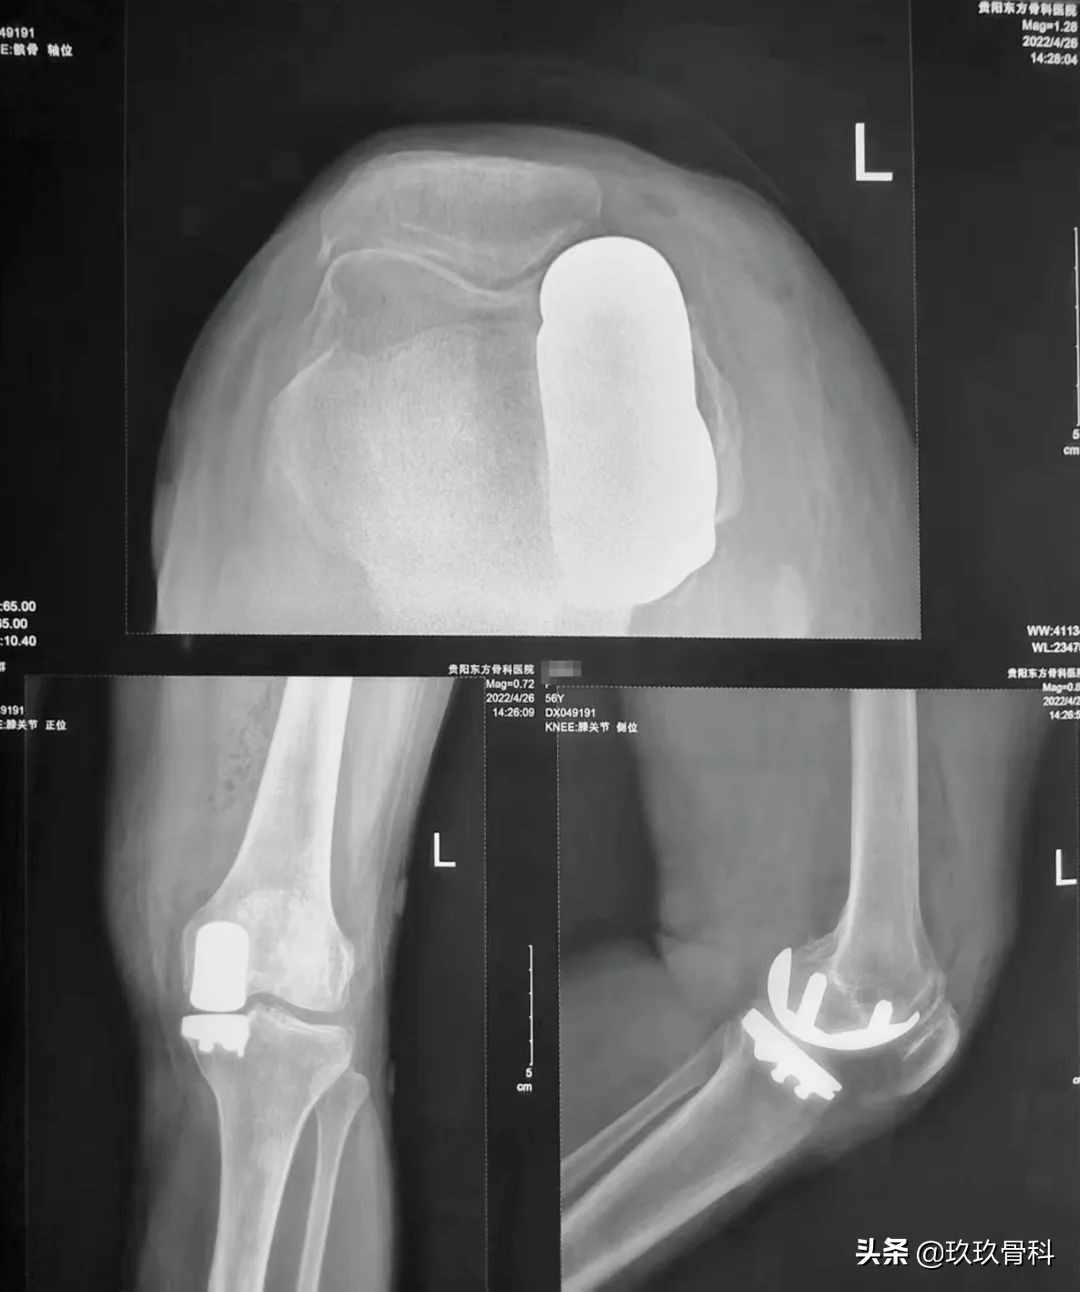

术后影像